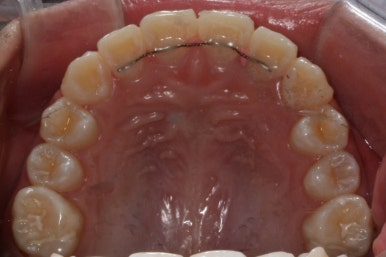

초진 시의 모습입니다.

11살의 어린이였기에 몇 군데 아직 유치가 남아있었습니다. 영구치가 모두 나오지 않았죠. 덧니가 있고 치열이 고르지 못하더라도 일반적으로 영구치가 더 나온 후에 연산동덧니교정 하는 것을 권해드립니다.

첫 장치 부착한 모습입니다.

아직 유치가 몇 개 남아있기에 장치가 전체적으로 부착되지 않습니다. 우선 앞니 4개만 먼저 치열을 맞추고 위쪽 어금니는 후방 이동을 해주면서 교합을 맞추며 덧니가 내려올 공간을 확보합니다.